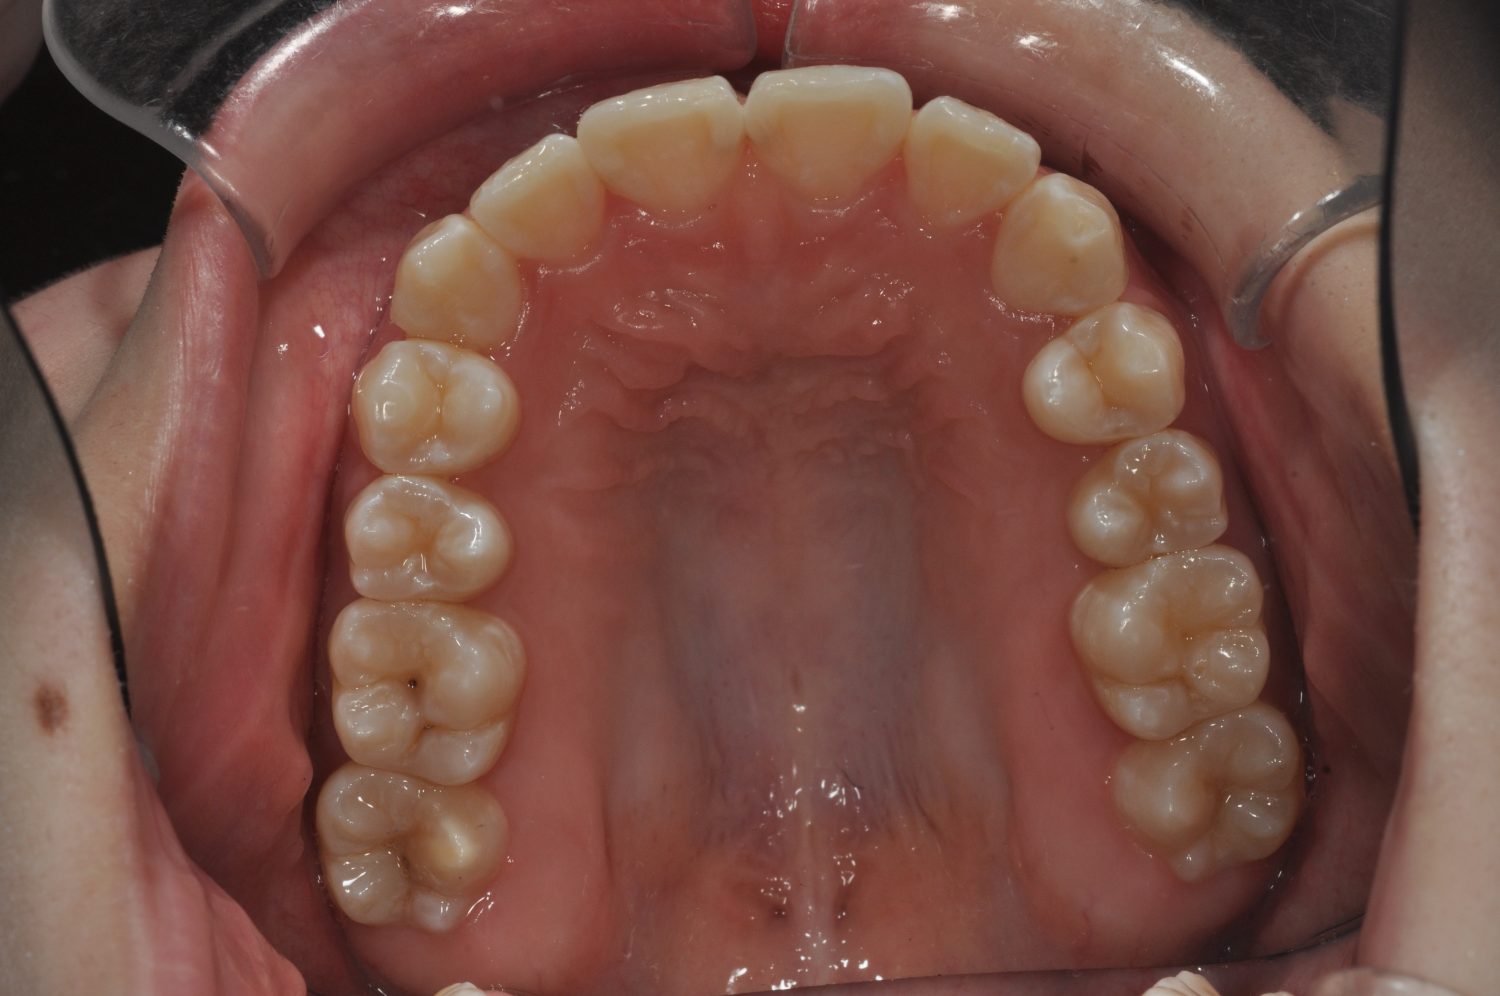

| 主訴 | 口上下顎のガチャガチャが気になる |

| 治療内容 | 歯冠幅径が大きいことから、IPRを併用した非抜歯治療 |

Ⅰ期治療で前歯部反対咬合をセクショナルアーチとMPAを使用して改善した後、成長観察を行っていました。永久歯が萌出したため、Ⅱ期治療を開始することとなった。上下顎とも骨格的に問題がなかったため、非抜歯で治療を行った。